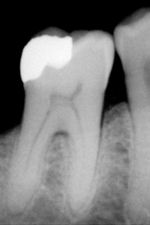

An X-ray showing enamel and dentin replaced by an amalgam restoration